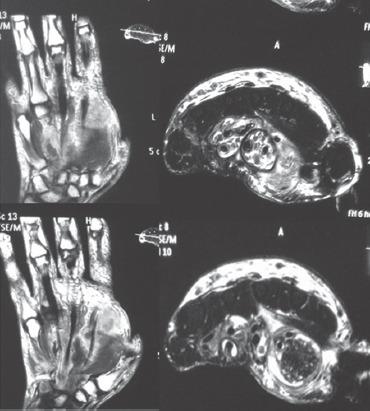

We present case of 58-year-old male patient with swelling over thenar region of left hand where the initial fine needle aspiration cytology (FNAC) report suggested diagnosis of ganglion/synovial cyst, but the patient did not improve with conservative treatment. FNAC was repeated which showed granulomatous inflammation consistent with the clinical diagnosis of tuberculosis and antitubercular therapy for 9 months was given. Swelling disappeared and normal range of movements was attained in adjacent joints at final follow-up of 12 months from initiation of antitubercular treatment (ATT).

我们报告一例58岁男性患者,其左手大鱼际区域肿胀。最初的细针穿刺抽吸细胞学检查(FNAC)报告提示诊断为腱鞘囊肿/滑膜囊肿,但患者经保守治疗后并无改善。重复进行FNAC检查,结果显示为肉芽肿性炎症,与结核病的临床诊断相符,遂给予9个月的抗结核治疗。在开始抗结核治疗(ATT)12个月的最终随访中,肿胀消失,相邻关节恢复了正常活动范围。